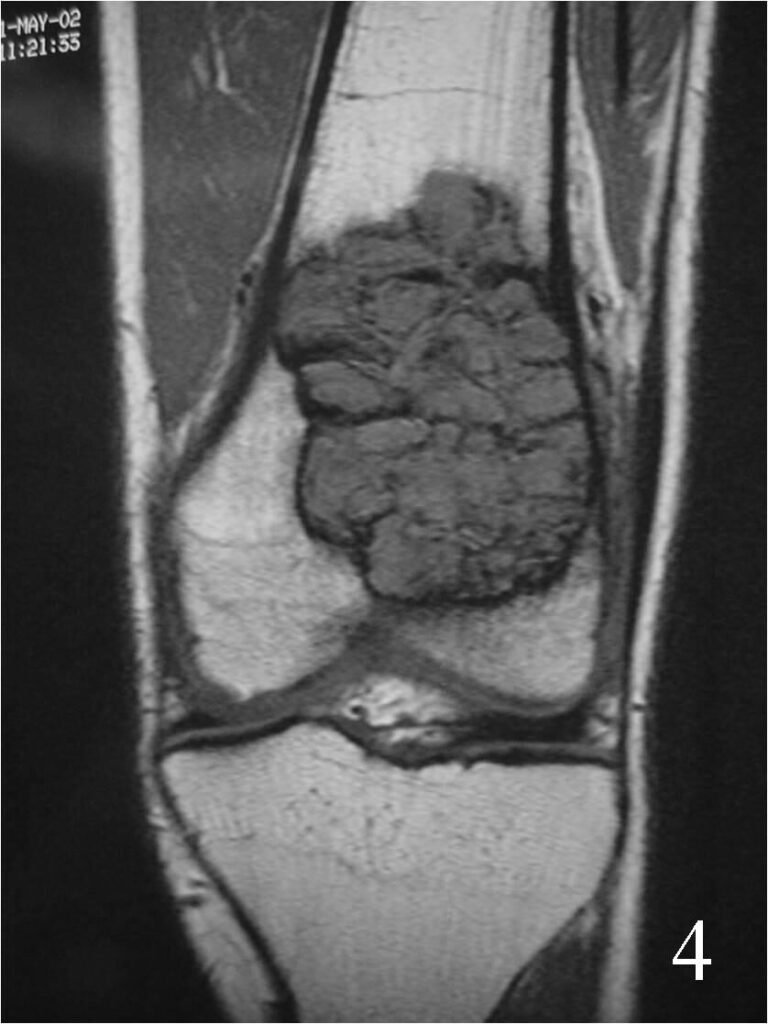

- They will be low to intermediate on T1-weighted images, and intermediate to high on T2-weighted images (Fig. 4, 5, 6)

Fig. 4 Coronal T1 MRI of the knee demonstrates a low signal lesion in the distal femur.